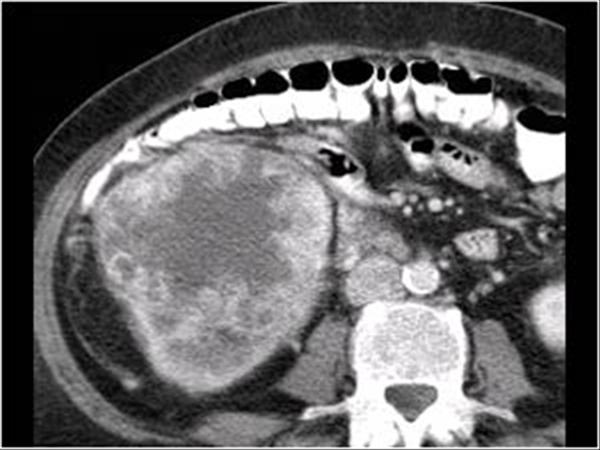

RCC

» Thông tin: Nữ giới – 69 tuổi.

» Lâm sàng: Đái máu.

# Ung thư biểu mô tế bào thận phải (Renal cell carcinoma – RCC) / Huyết khối tĩnh mạch chủ dưới.